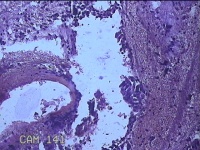

宫颈管内膜

性别

女

年龄

44岁

临床诊断

子宫异常出血;子宫肌瘤;子宫内膜息肉

一般病史

阴道流血1月。

标本名称

大体所见

纱布一块,内有灰白暗红色不规则碎组织1.5x1x0.2cm一堆。